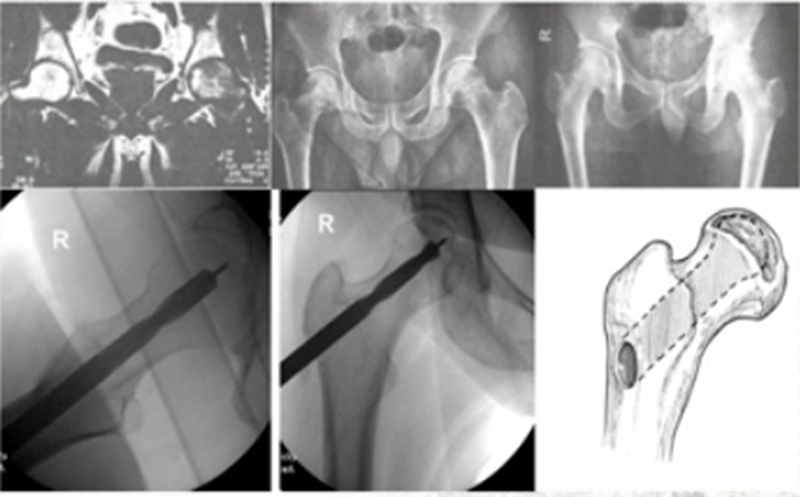

2、细孔径双通道钻孔髓芯减压术

1987年起,浙江省中医院团队设计粗隆下5mm孔径、双通道、股骨头倒V形钻孔加丹参灌注,治疗成人股骨头坏死54例,经过2~8.5年临床观察显示,该方法疗效明显,总优良率达81%,Ⅰ~Ⅱ期优良率达94%。

该疗法手术创伤小、难度小,对患者负影响较小,术后机能恢复快,易于接受。